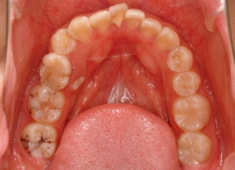

治療前